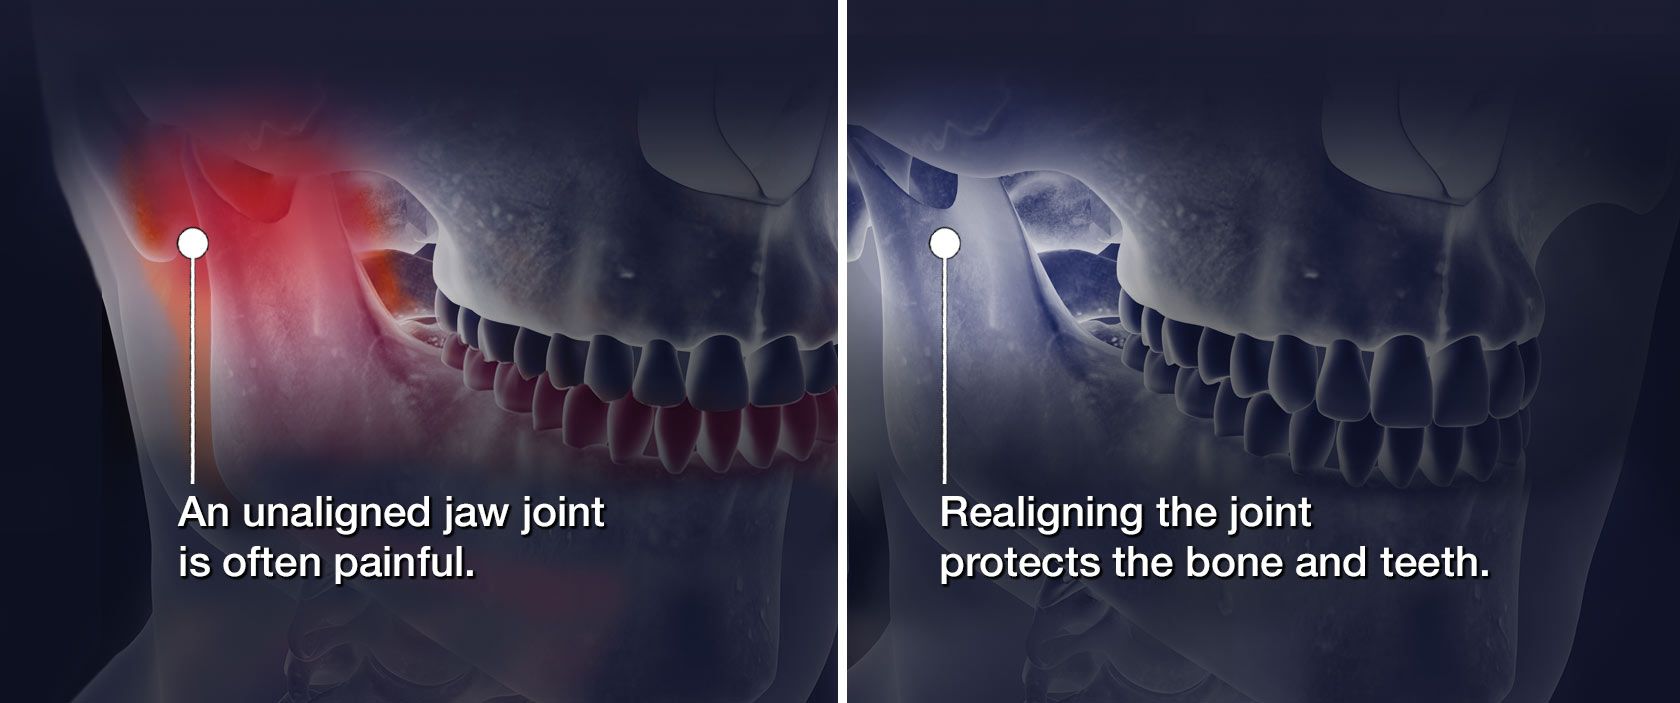

Our dentists offer TMD treatment through oral appliance therapy. Oral appliances are also sometimes known as splints.

Oral appliance therapy is a simple yet effective way to reposition your jaw and alleviate the effects of your temporomandibular joint problems.

This treatment keeps you from grinding and clenching, allowing your inflammation to subside.

Prevention and Protection: See How Oral Appliance Therapy Works

Our experienced Belmont, NC, dentists may be able to treat your TMD with oral appliance therapy alone. A mouthguard can relieve the pressure on your jaw joint, leading to reduced or eliminated symptoms.

While you may feel nervous, let us reassure you: many patients can be treated using just a mouthguard.

Typically, temporomandibular joint surgery is only used as a last resort. We would consider it only after you have exhausted all the options, such as an oral appliance (also known as a splint).